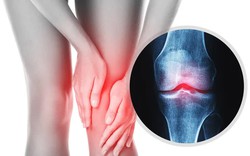

• Cơ xương khớp